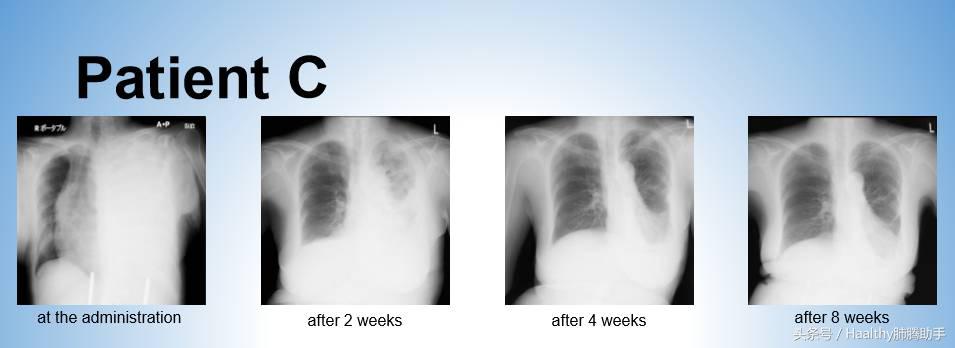

患者C 女性 69岁

患者C的胸腔积液发现腺癌细胞,因此进行EGFR、ALK基因检测,患者C也没有等待基因检测结果。

在初诊4 天后开始一线化疗,化疗方案为培美曲塞+卡铂+贝伐珠单抗。患者C接受6周期化疗后疾病部分缓解,并继以培美曲塞+贝伐珠单抗维持治疗。

患者C在初始化疗开始后130天后仍然存活,疾病没有进展。患者C基因检测结果显示:EGFR L858R突变。